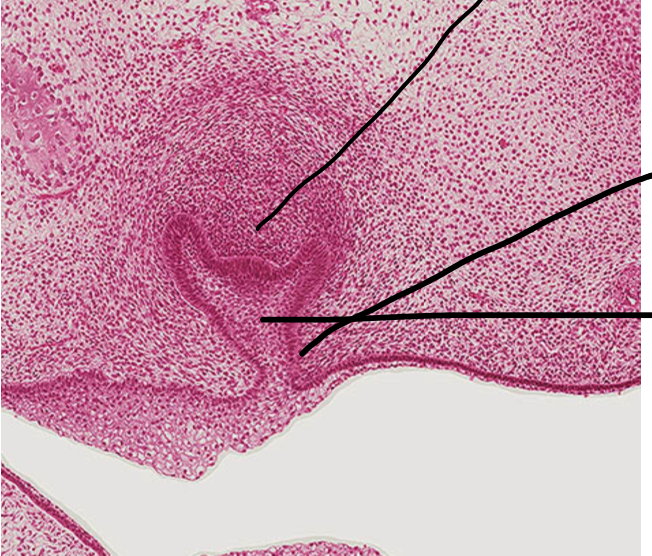

1

Q

what stage is this tooth germ?

A

cap stage